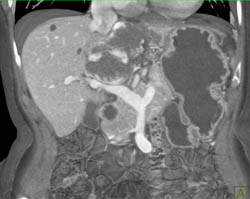

Partial Thrombosis of the Splenic Vein